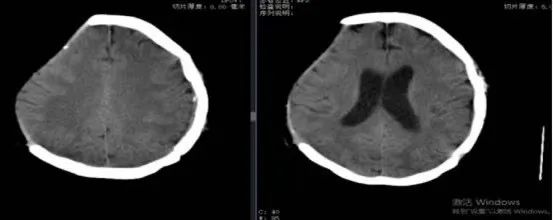

患者女性,59歲,2024年4月3日因外傷后致右側(cè)額顳頂部急性硬膜下血腫伴腦疝形成,急診行右側(cè)開顱血腫清除術(shù)+去骨瓣減壓術(shù)。術(shù)后患者轉(zhuǎn)危為安,恢復(fù)良好出院。但右側(cè)頭部遺留顱骨缺損,不僅影響美觀,而且會給患者帶來不安全感,甚至引起顱骨缺損綜合征、腦萎縮、外傷性癲癇等多種不良后果。

此次患者來到我院,想通過進一步治療解決顱骨缺損問題。神經(jīng)外科團隊仔細評估了患者病情并制定了詳細的手術(shù)方案。術(shù)前進行了頭顱CT掃描,利用計算機構(gòu)建出患者顱骨缺損三維重建圖。